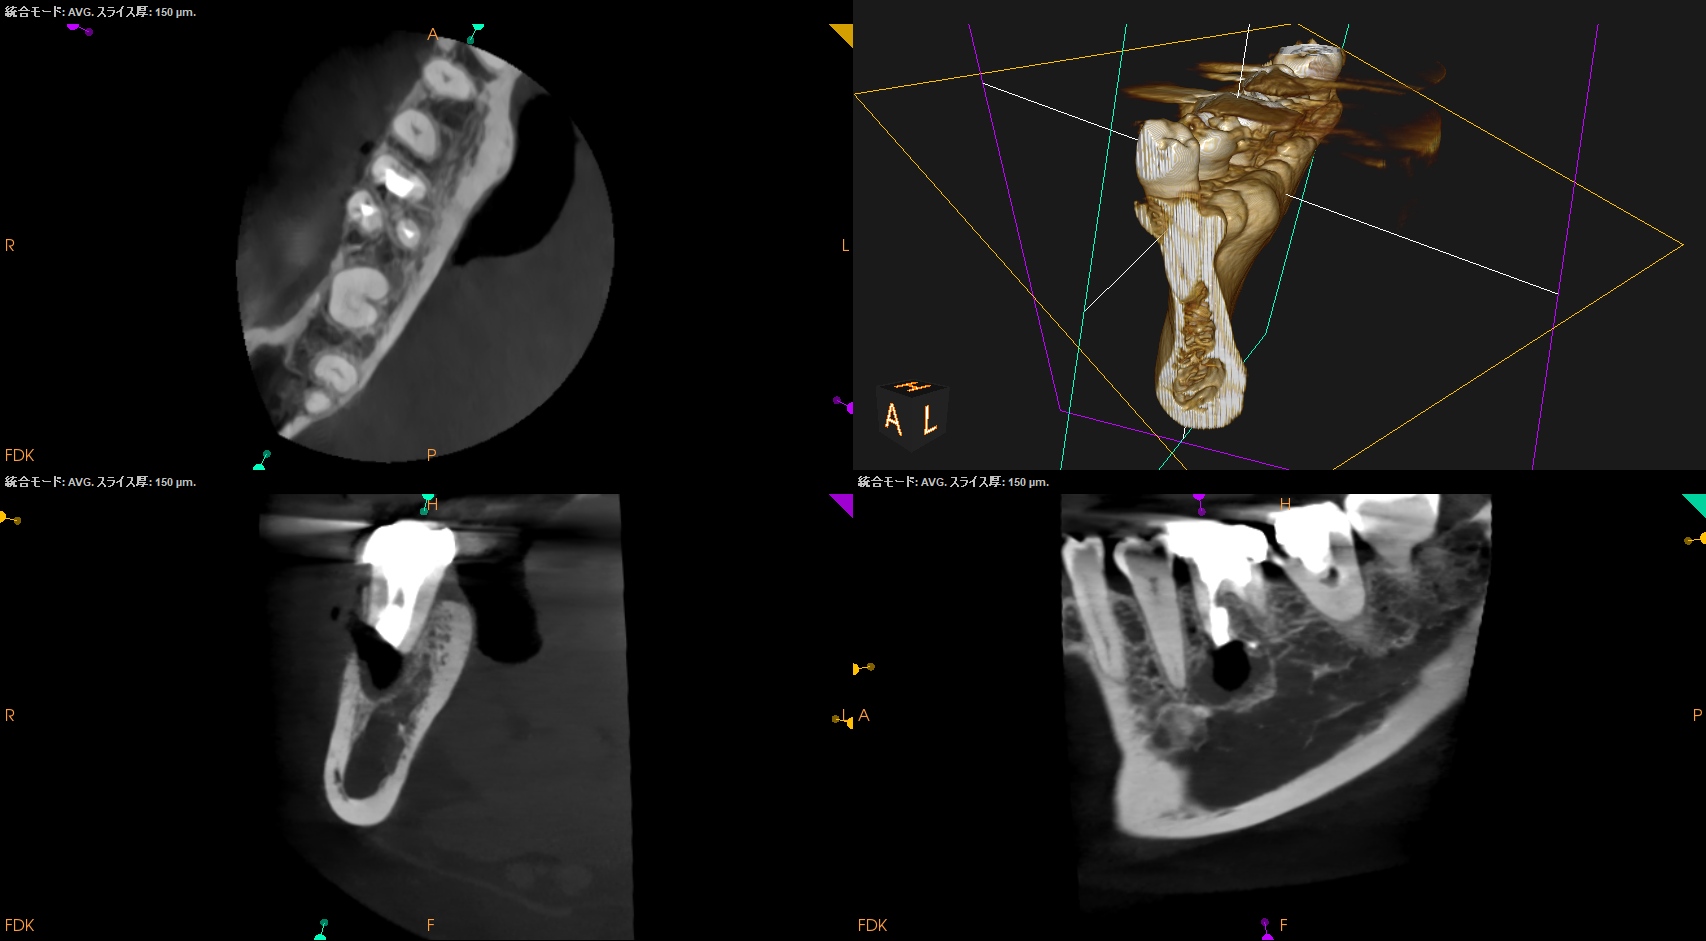

#30 初診時検査(2024.6.19)

MB

ML

D

Radix

M根の根尖部に大きな病変がある。

そして、すでに根管形成が太くなされている。

CEJの10.5mm下方にApexがあり、

そこを3mm切断しようと思えば、5.6mmの切断幅がある。

MB,MLは近接しているのでイスムスの形成は問題なくできそうである。

またDにも根尖病変があるように見えるが、これはM根から由来しているのかもしれない。